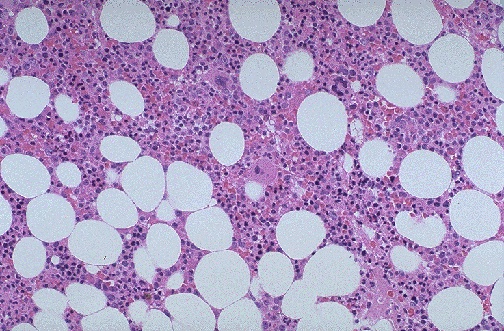

| This is the appearance of normal bone marrow at medium magnification, with cellular marrow and adipose tissue. The large multinucleated cells are megakaryocytes. The erythroid islands and granulocytic precursors form the bulk of the cellular component. This marrow is taken from the posterior iliac crest in a middle aged person, so it is about 50% cellular, with steatocytes admixed with the marrow elements. |